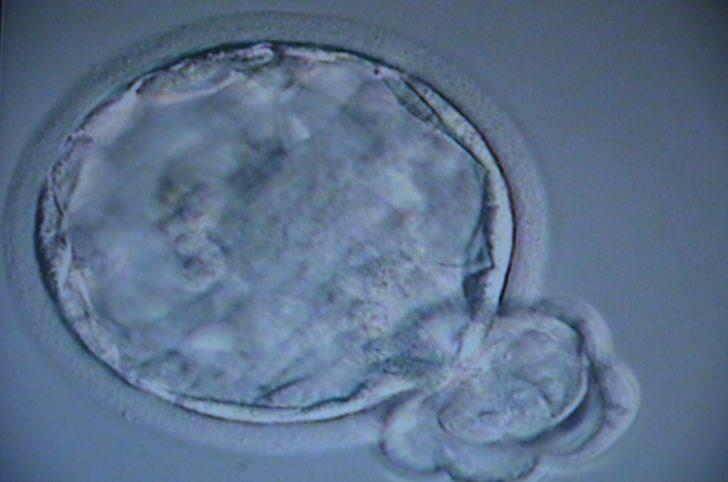

Kadın Doğum ve Tüp Bebek Uzmanı Doç. Dr. Gökalp Öner, menopoza giren ev kadını E.M'ye kök hücre nakli yaptı. Hücre nakli ile E.M'nin anne olma umudu doğdu. Doç. Dr. Öner, Türkiye'de ilk defa menopoza girmiş hastaya kök hücre transferi yaptıklarını söyledi. Doç. Dr. Öner, hastanın kendi yağ dokusundan yağlarını alıp, bunu 2 saat süren bir işlemden geçirdikten sonra, kök hücrelerini kendi yumurtalarına anestezi altında ultrason eşliğinde enjekte ettiklerini kaydetti. Öner, "Bu, yurt dışında sayılı merkezlerde yapılan, yumurta rezervi azalmış, hatta menopoza girmiş hastalarda uygulanan başarılı bir yöntem. Biz bunu Türkiye'de ilk kez yapmanın gururunu yaşıyoruz. Hastamızın inşallah güzel haberlerini de alacağız. Gebelik haberini de inşallah buradan paylaşacağız. Bu hiç umudu kalmamış, tüp bebekte bile gebelik umudu sıfır olan, yumurta rezervi tamamen tükenmiş hastalar için yeni bir umut oldu. Bunu da Kayseri'de yapmanın gururunu yaşıyoruz" şeklinde konuştu.

Kök hücre nakli yaptıkları hastayı takibe aldıklarını kaydeden Öner, "Yumurtalarımızı elde edeceğiz. Sonrasında da tüp bebek işlemiyle embriyomuzu elde ettikten sonra inşallah gebelik haberini vereceğiz. 6 ay içinde hastamızı sürekli olarak takibe alacağız. Kök hücreler ortalama 2 ya da 3 ayın sonunda yumurta oluşmaya başlıyor. Bu yumurtaları biz topladıktan sonra tüp bebek yapacağız. Kök hücre için bir yaş sınırı var. Genelde 47 yaşından sonraki hasta grubunda biz yumurta bile elde etsek kaliteli bir embriyo elde etme imkanı yok. Onun için biz daha çok 47 yaşın altındaki gruba kök hücre uyguluyoruz" ifadelerini kullandı.